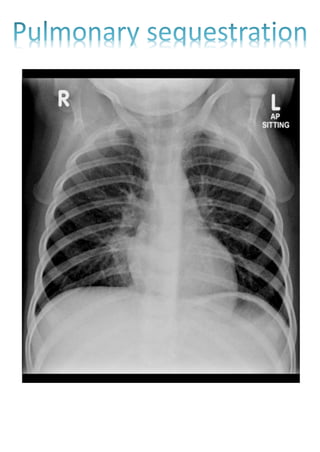

RESPIRATORY DISTRESS SYNDROME

WHITE OUT LUNG/GROUND GLASS APPEARANCE OF

LUNG/ reticulonodular appearance

(due to absence of air entry into the lung)

Air bronchogram

(due to air in the bronchus and bronchioles)

Bilateral involvement

Preterm

Alveoli are not

expanded, air is entering

all the airways  even

the smallest bronchioles

Ground glass

appearance can be

seen also in

1)RDS

2)PULMONARY

ALVEOLAR

PROTEINOSIS

3)OBSTRUCTIVE

TAPVC